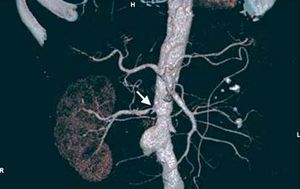

Surgical Treatment

Surgical treatment is indicated in the concomitant repair of the aorta due to aortoiliac or aneurysmal occlusive disease, adverse anatomy or involvement of the complex renal arteries (aneurysms, polar arteries, segmental artery lesions), failed percutaneous revascularization or the impossibility of treating restenosis by percutaneous techniques. Revascularization can be carried out by means of endarterectomy (renal or transaortic), aortorenal bypass or extraanatomic bypass (hepatorenal or splenorenal), reimplantation, autotransplantation, or ex vivo surgery for the repair of segmental arteries. The hypertensive kidney with renin hypersecretion may require nephrectomy. The mortality observed in surgical treatment is influenced by the comorbidities associated with atherosclerosis, as well as the complexity of the reconstruction, and is higher in combined aortorenal surgery (Figure 9). Hansen and Dean105 reported an operative mortality of 5.3% in patients undergoing combined surgery, as compared to 1.7% and 0.7% in procedures limited to the renal artery and aorta, respectively. Weibull et al106 randomized 58 patients to surgical or percutaneous treatment, with equivalent results in terms of survival and blood pressure control. In Spain, the progressive disuse of revascularization surgery in favor of percutaneous procedures has resulted in the circumstance that the former is being performed in increasingly fewer centers.

Figure 9. Example of left aortorenal bypass (arrows) in an aortobifemoral revascularization procedure to treat Leriche syndrome.